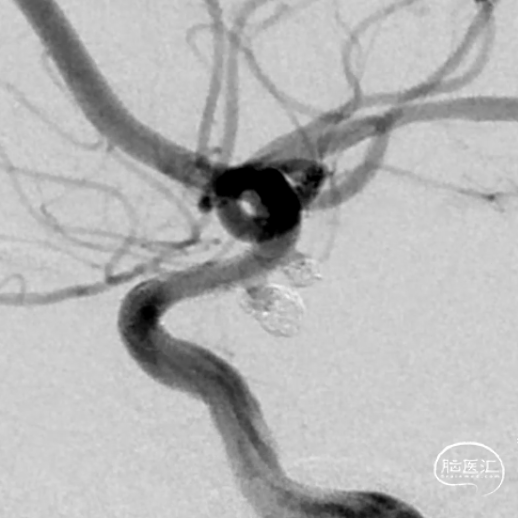

这是一根通桥银蛇DA远端通路导引导管,在Sim II和导丝到位后,通桥银蛇DA远端通路导引导管能够非常容易地顺着架设的道路直接放到位,然后进行后续使用Pipeline血流导向密网支架来治疗复发动脉瘤的操作。我们可以看到在Pipeline的到位以及释放的过程中,通桥银蛇DA远端通路导引导管都非常稳定,能够获得比较满意的结果。

释放PED过程中,通桥银蛇DA远端通路导引导管头端非常稳定。

术前

术后